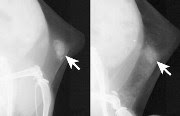

A new mammography technique detects microcalcifications in both normal mice (left) and those with dense mammary tissue (right).

Detecting breast cancer in women with dense mammary tissues could become more reliable with a new mammogram procedure that researchers have now tested in pre-clinical studies of mice. In their report in the journal ACS Nano, they describe injecting gold nanoparticles in mammary tissue to enhance the imaging of early signs of breast cancer.

The researchers boosted the contrast of mammography X-rays by modifying gold nanoparticles with molecules that bind specifically to microcalcifications. They injected a low dose of these nanoparticles into the mammary glands of mice with dense tissue. The engineered particles made the microcalcifications brighter on the X-rays -- and therefore, easier to distinguish. The mice showed no obvious side effects. Although further research would be required, the scientists say the technique could eventually translate into more reliable breast cancer detection for women with dense mammary tissue.